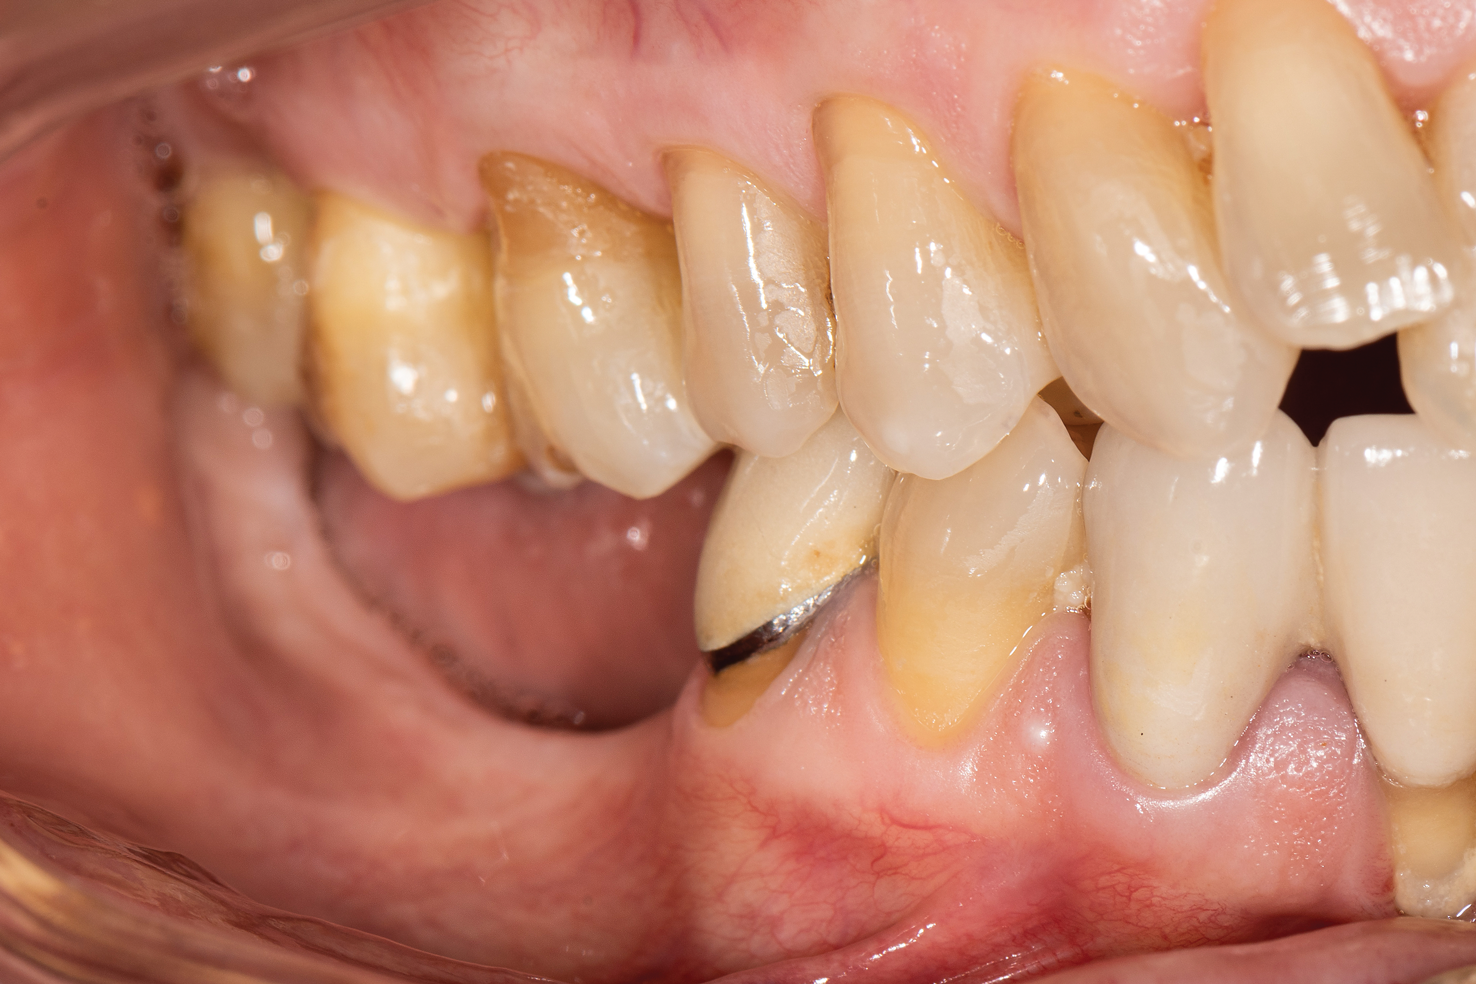

Patient 2, a 50-year-old woman with minor osteoporosis, needed grafting because of  severe atrophy in the right mandible (Siebert class II) (Figure 11 and Figure 12). The  titanium mesh mesh was designed using CAD/CAM tech- nology in the same manner as in Case I. In this case, a mix of autologous and xeno- graft was used. Re-entry time was 8 months. The same protocol was followed as in Case 1 (Figure 13 through Figure 17).

Fig 11. Intraoral condition showing severe atrophy of the right side of the mandible.

Figure 11

Fig 13. After lingual flap was released, donor site preparation was performed.

Figure 13